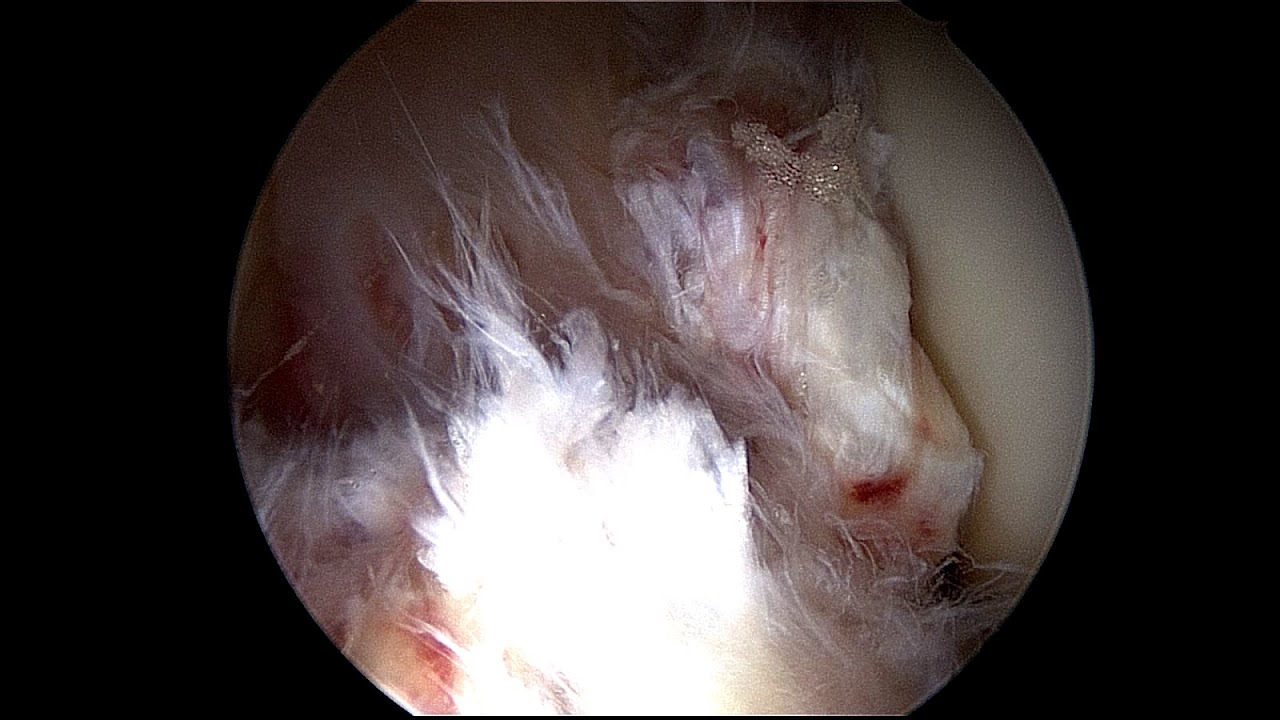

Surgery

If surgery is decided upon, either because obvious instability interferes with activities of daily living, or because the knee is subject to repeated, severe, provocative maneuvers, such as the case of the competitive athlete involved in cutting and rapid deceleration etc., then several issues need to be decided upon.

These issues are fully explored in ACL Reconstruction.

There are around 200,000 ACL tears each year in the United States, with over 100,000 ACL reconstruction surgeries per year. Over 95% of ACL reconstructions are performed in the outpatient setting. The most common procedures performed during ACL reconstruction are partial meniscectomy and chondroplasty.